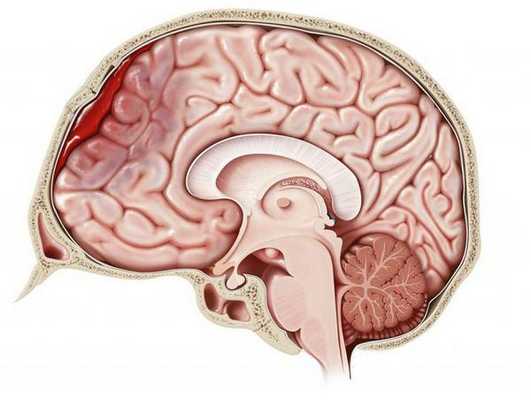

Сдавление головного мозга

Сдавление головного мозга развивается более чем в 55% случаев черепно-мозговой травмы. Чаще всего причиной сдавления головного мозга становится внутричерепная гематома (внутримозговая, эпи- или субдуральная). Опасность для жизни пострадавшего представляют стремительно нарастающие очаговые, стволовые и общемозговые симптомы. Наличие и продолжительность т. н. «светлого промежутка» — развернутого или стертого — зависит от степени тяжести состояния пострадавшего.

На КТ определяют двояковыпуклую, реже плоско-выпуклую ограниченною зону повышенной плотности, которая примыкает к своду черепа и локализируется в пределах одной или двух долей. Однако, если источников кровотечения несколько, зона повышенной плотности может быть значительного размера и иметь серповидной форму.